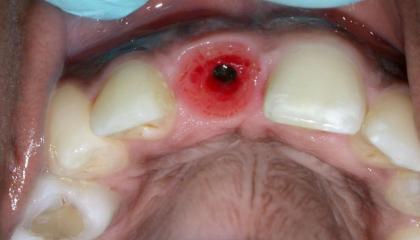

Single Dental Implant